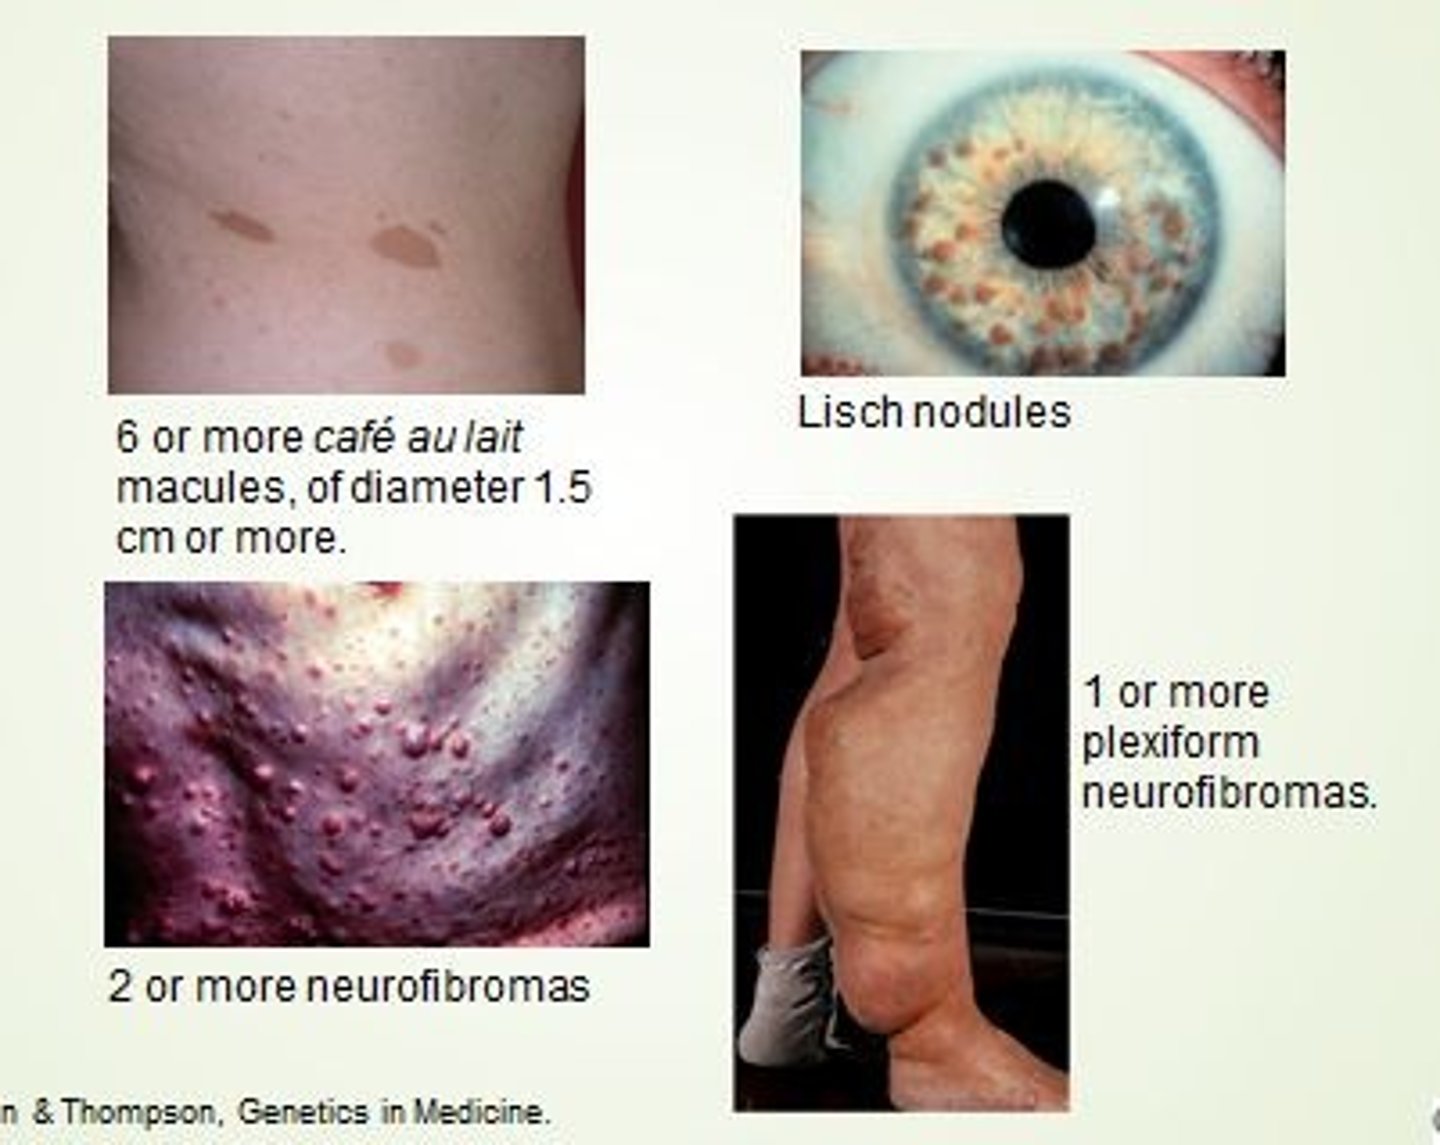

Cafe-au-lait spots, Lisch nodules (iris hemartoma), cutaneous neurofibromas

Neurofibromatosis Type I, pheochromocytoma, optic gliomas

Cafe-au-lait spots (unilateral), polyostotic fibrous dysplasia, precocious puberty, multiple endocrine abnormalities

McCune-Albright syndrome

(mosaicism, G-protein signaling mutation)